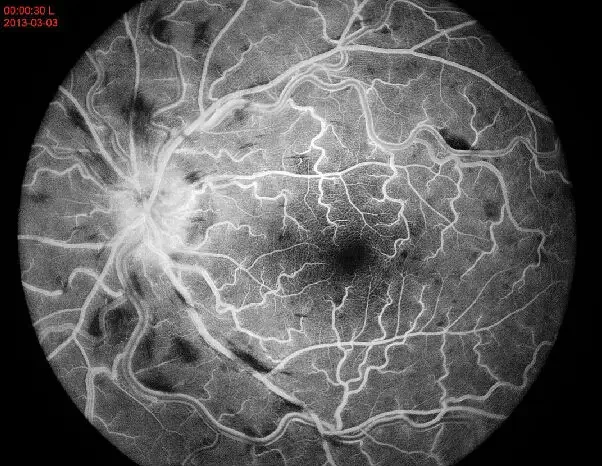

APS-BRE оборудование для оптометрии глаз ретривная - Инструменты для измерения и анализа

APS-BRE оборудование для оптометрии глаз, ретривная камера- Фото №1APS-BRE оборудование для оптометрии глаз, ретривная камера- Фото №2APS-BRE оборудование для оптометрии глаз, ретривная камера- Фото №3APS-BRE оборудование для оптометрии глаз, ретривная камера- Фото №4APS-BRE оборудование для оптометрии глаз, ретривная камера- Фото №5